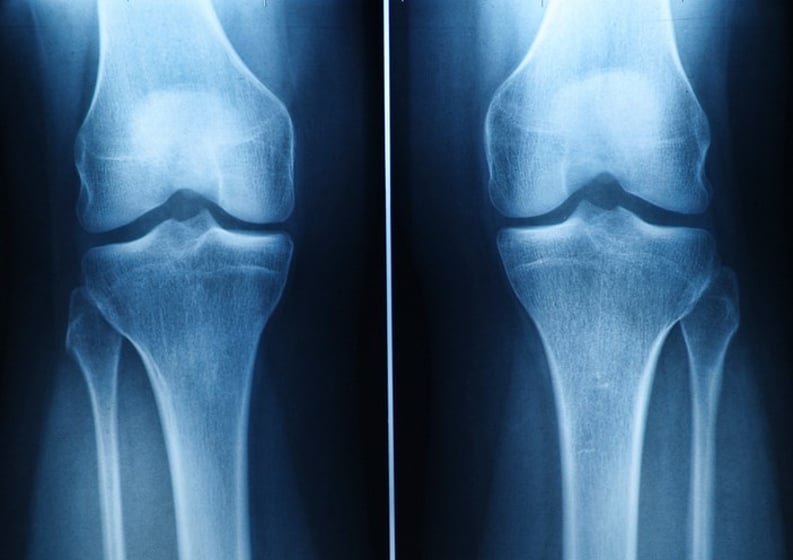

The program aims to provide students with the technical expertise needed for entry-level radiographers, along with communication, critical thinking, and problem-solving skills. Students will learn patient positioning, technical parameters, and radiation protection, and will be able to adapt procedures for non-routine cases and evaluate image quality.